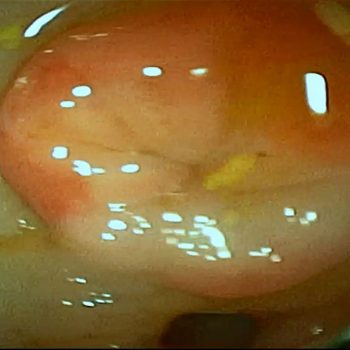

Diagnostyka chorób górnego odcinka przewodu pokarmowego (Gastroskopia, Ezofagoskopia, Gastroduodenoskopia)

Rozpoznawanie ostrych i przewlekłych chorób przełyku, żołądka i dwunastnicy

Usuwanie ciał obcych z przełyku i żołądka

Pobieranie wycinków ze zmian chorobowych do badania histopatologicznego

Usuwanie polipów zapalnych

Balonikowanie zwężeń przełyku (nabytych lub wrodzonych)